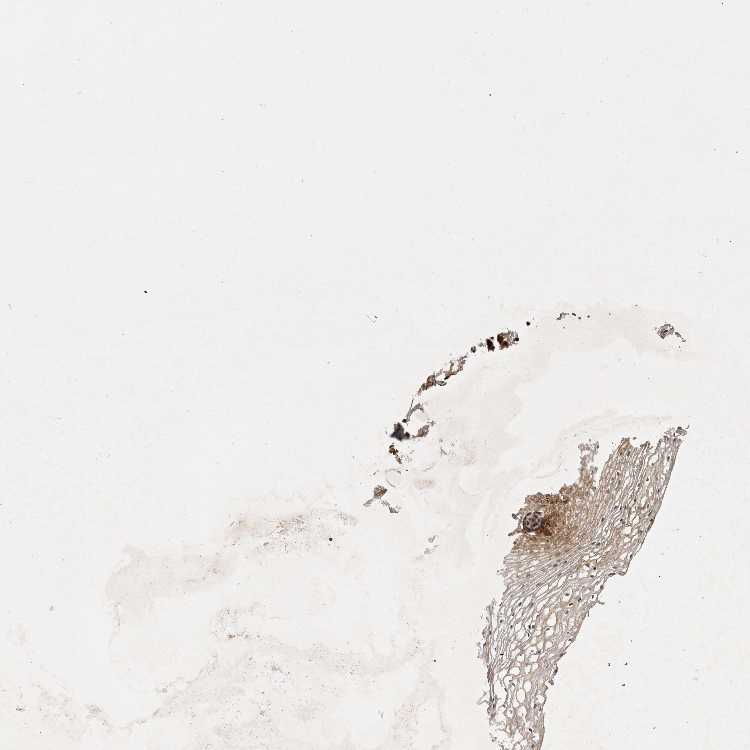

VAGINA - Antibody stainingi

Antibody staining in the annotated cell types in the current human tissue is reported as not detected, low, medium, or high, based on conventional immunohistochemistry profiling in selected tissues. This score is based on the combination of the staining intensity and fraction of stained cells.

Each image is clickable and will lead to virtual microscopy that enables deeper exploration of all samples and also displays staining intensity scores, fraction scores and subcellular localization as well as patient and tissue information for each sample.

Antibody HPA025715

Squamous epithelial cells Medium